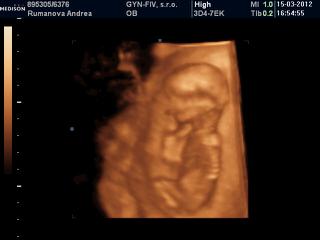

@andrea_stella jemine to je jake mrnave ja som to este veru nevidela taketo male na 4D 😀 😀 😀 nema chybu martanko maly resp. martanka tak by si to chcela ze 😀 😀 😀